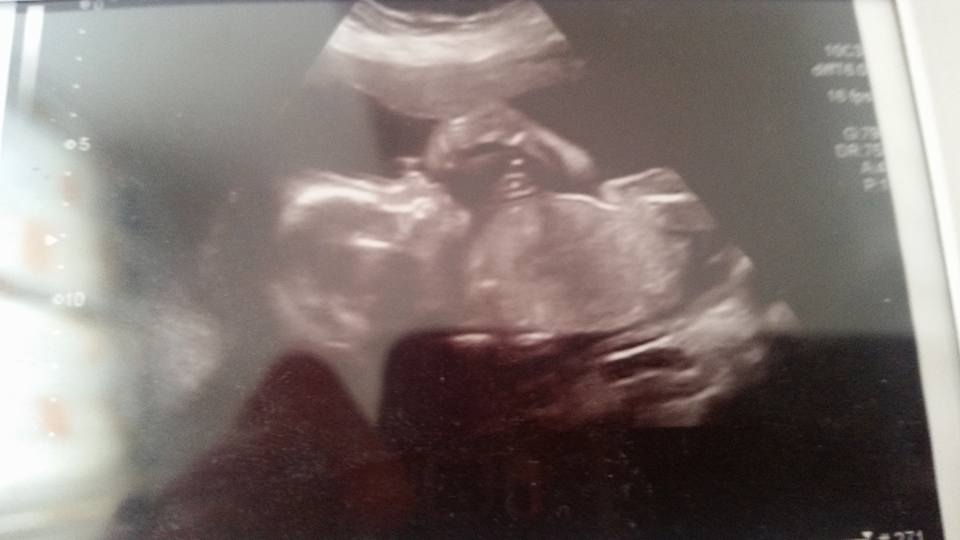

Immy’s 20 week scan